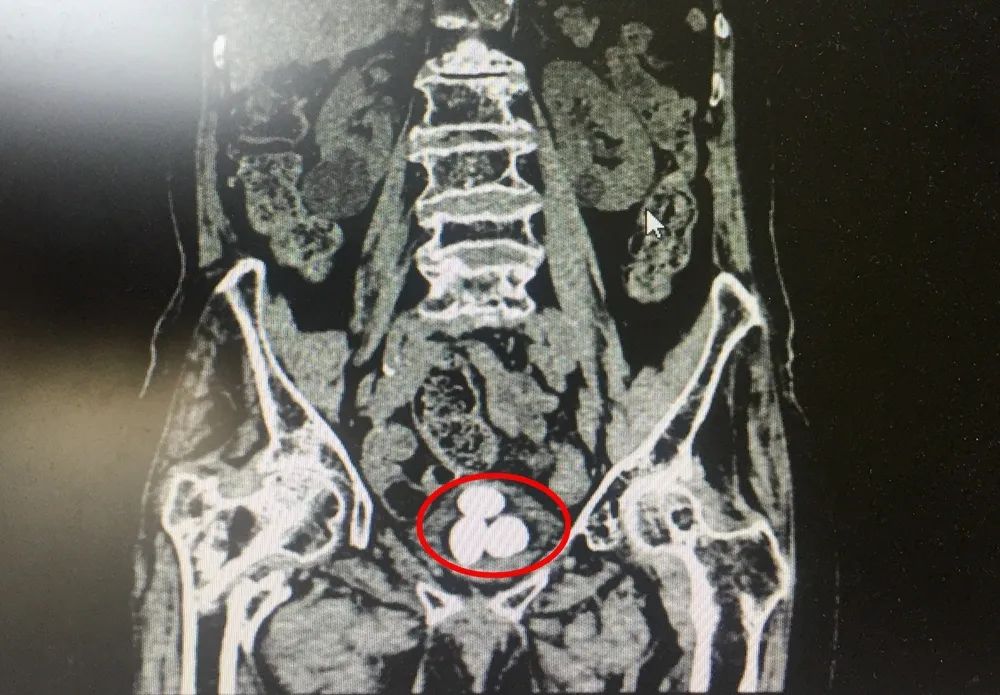

99歲的啟東老人楊奶奶,2年多前因?yàn)樗麑?dǎo)致了右側(cè)髖關(guān)節(jié)骨折,造成右腿畸形愈合,日常行走不便,長期臥床。之后,老人開始出現(xiàn)間斷血尿,到當(dāng)?shù)蒯t(yī)院檢查后發(fā)現(xiàn)患上了膀胱結(jié)石,因?yàn)闂钅棠棠挲g較大,手術(shù)風(fēng)險(xiǎn)高,醫(yī)生建議藥物治療,對(duì)癥消炎、止血。今年4月,楊奶奶再次出現(xiàn)了血尿情況,尿液深紅色,還有血塊。這一次,家人還是帶她去醫(yī)院保守治療,結(jié)果10多天了依然不見改善。持續(xù)的血尿,伴隨著尿頻、尿痛,讓老人的生活深受困擾。這樣的長壽本是福氣,楊奶奶卻每日受著疾病煎熬,吃不下睡不著??粗赀~的母親痛苦難耐,楊奶奶的子女們也很揪心。到底還能不能做手術(shù)把結(jié)石取出來?帶著這樣的疑問,在住進(jìn)南通瑞慈醫(yī)院泌尿外科病房之前,子女們咨詢了多家醫(yī)院,卻都被婉言謝絕。▲影像資料顯示,楊奶奶的膀胱幾乎被三顆結(jié)石占滿

泌尿外科馬建國主任回憶老人病情時(shí)說,楊奶奶長期臥床,結(jié)石越長越大。入院后的檢查結(jié)果顯示,老人的膀胱內(nèi)長了三顆結(jié)石,最大的直徑達(dá)到4厘米,有鴿子蛋那么大,膀胱基本上被結(jié)石占滿了。據(jù)馬主任介紹,膀胱結(jié)石目前多采用鈥激光微創(chuàng)碎石手術(shù),手術(shù)本身并不復(fù)雜,但楊奶奶已是99歲高齡,心、腦、肺功能都不是太好,基礎(chǔ)情況不容樂觀,無論是術(shù)中的麻醉風(fēng)險(xiǎn)、發(fā)生心腦血管意外風(fēng)險(xiǎn),還是術(shù)后出現(xiàn)并發(fā)癥的風(fēng)險(xiǎn),都比普通病人高出了一大截。“高齡不是絕對(duì)的手術(shù)禁忌。如果繼續(xù)采取保守治療,老人未來的日子勢(shì)必沒有生活質(zhì)量可言。想讓她安享晚年,首先得想辦法幫她把這三顆頑石取出。風(fēng)險(xiǎn)是不可避免的,家屬也非常支持我們的工作。因此我們做了充分的術(shù)前準(zhǔn)備,組織多學(xué)科會(huì)診,評(píng)估手術(shù)耐受情況,完善檢查排除手術(shù)禁忌,又經(jīng)過一段時(shí)間調(diào)養(yǎng),幫助她改善心肺功能?!?/section>手術(shù)過程中還有一段小插曲,通常該類結(jié)石手術(shù)需要采取“截石位”,雙腿叉開抬高,類似于女性順產(chǎn)的姿勢(shì)。而老人因?yàn)橛彝然?,只能采取左腿抬高的“半截石位”手術(shù),增加了手術(shù)操作難度。憑借著多年的手術(shù)經(jīng)驗(yàn)和過硬的技術(shù),馬建國主任順利為楊奶奶完成了手術(shù)。